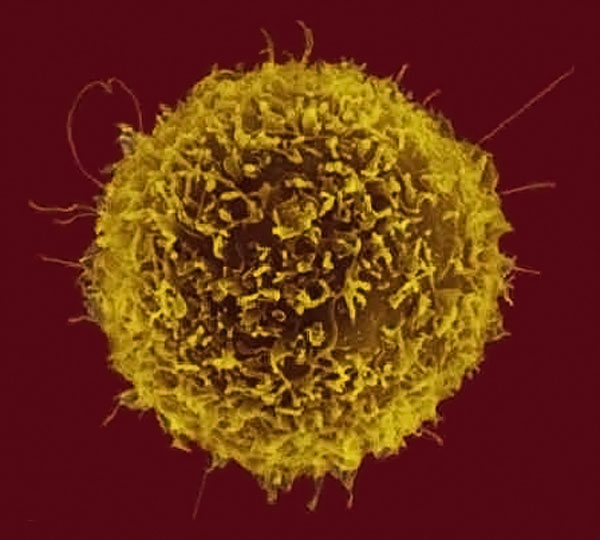

T淋巴细胞 – 91360智慧病理网